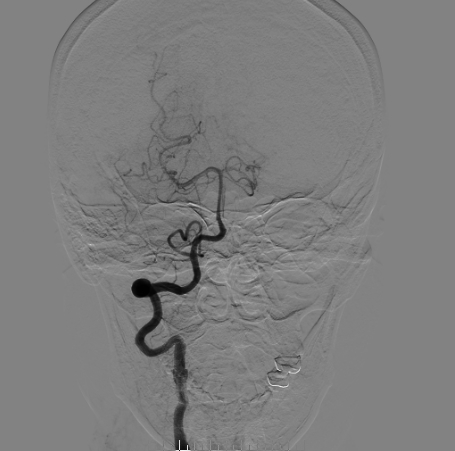

Vaso CT显示 畅医达(Choydar)血流导向装置 位置良好,完全覆盖瘤颈,长轴及横轴薄层均显示支架贴壁良好。

术后即刻正侧位造影显示载瘤动脉及远端分支显影无异常,瘤囊内可见明显造影剂滞留;Xper-CT未见出血。